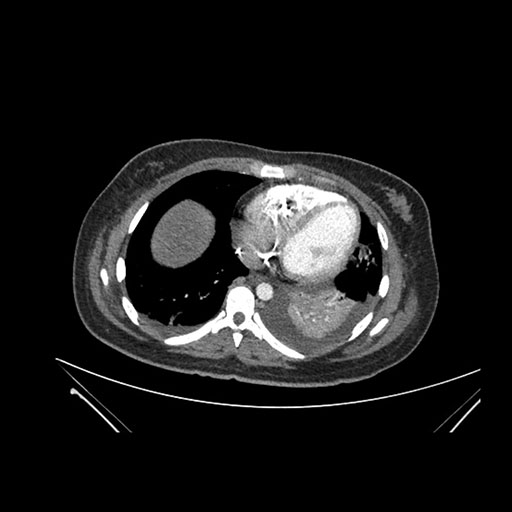

Imaging Analysis

Look through the patient's CT scan to identify any areas of concern for the necessary procedure.

Axial Venous

Based on initial findings, which issue(s) would you be most concerned about?